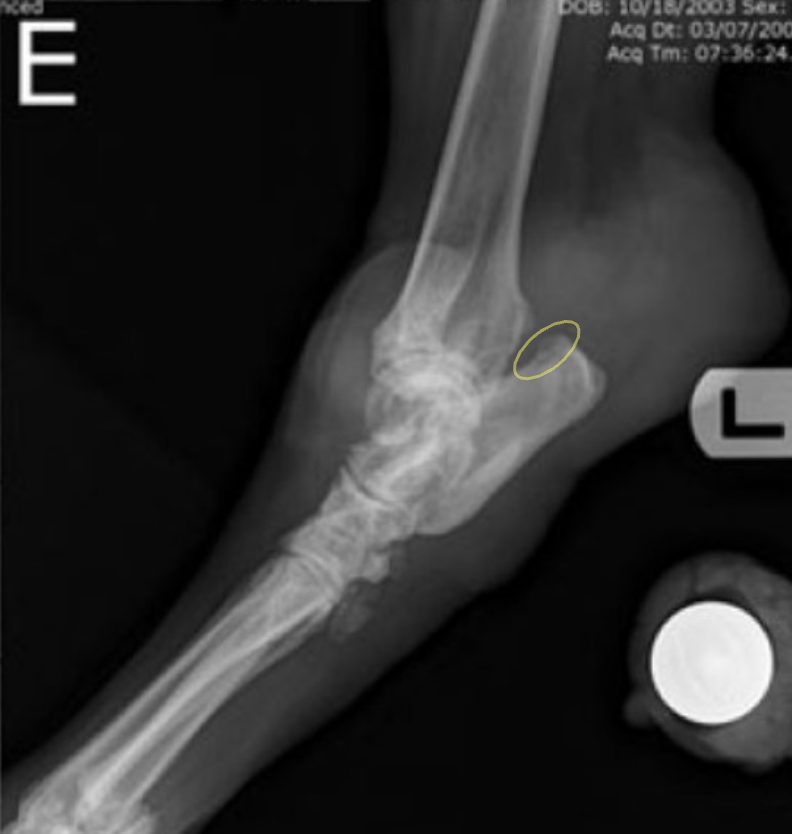

- ๊ด์ ์์ธก์์ ๋ผ์ ๋ณํ๊ฐ ๋ํ๋จ - subchondral bone & cortex์ lysis, new bone production

![]() | - ํ์ ์ด๊ฐ ๋ํ๋จ. - bone lysis๋ฅผ ์ผ์ผํค๋ฉด์ ์ฃผ๋ณ์ผ๋ก ์ ์ด๋จ. |